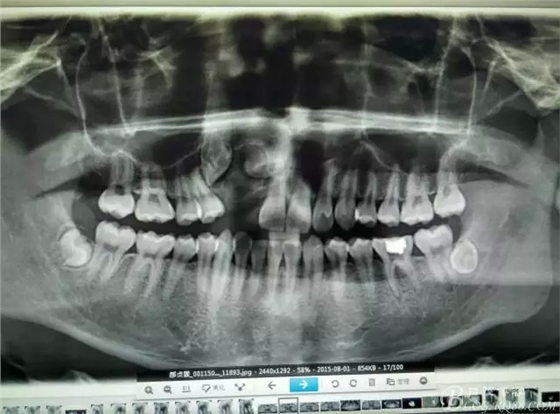

圖18.術(shù)后的全景片檢查:13牙冠與12重疊。11遠(yuǎn)中牙根區(qū)好像還有一顆牙齒喲